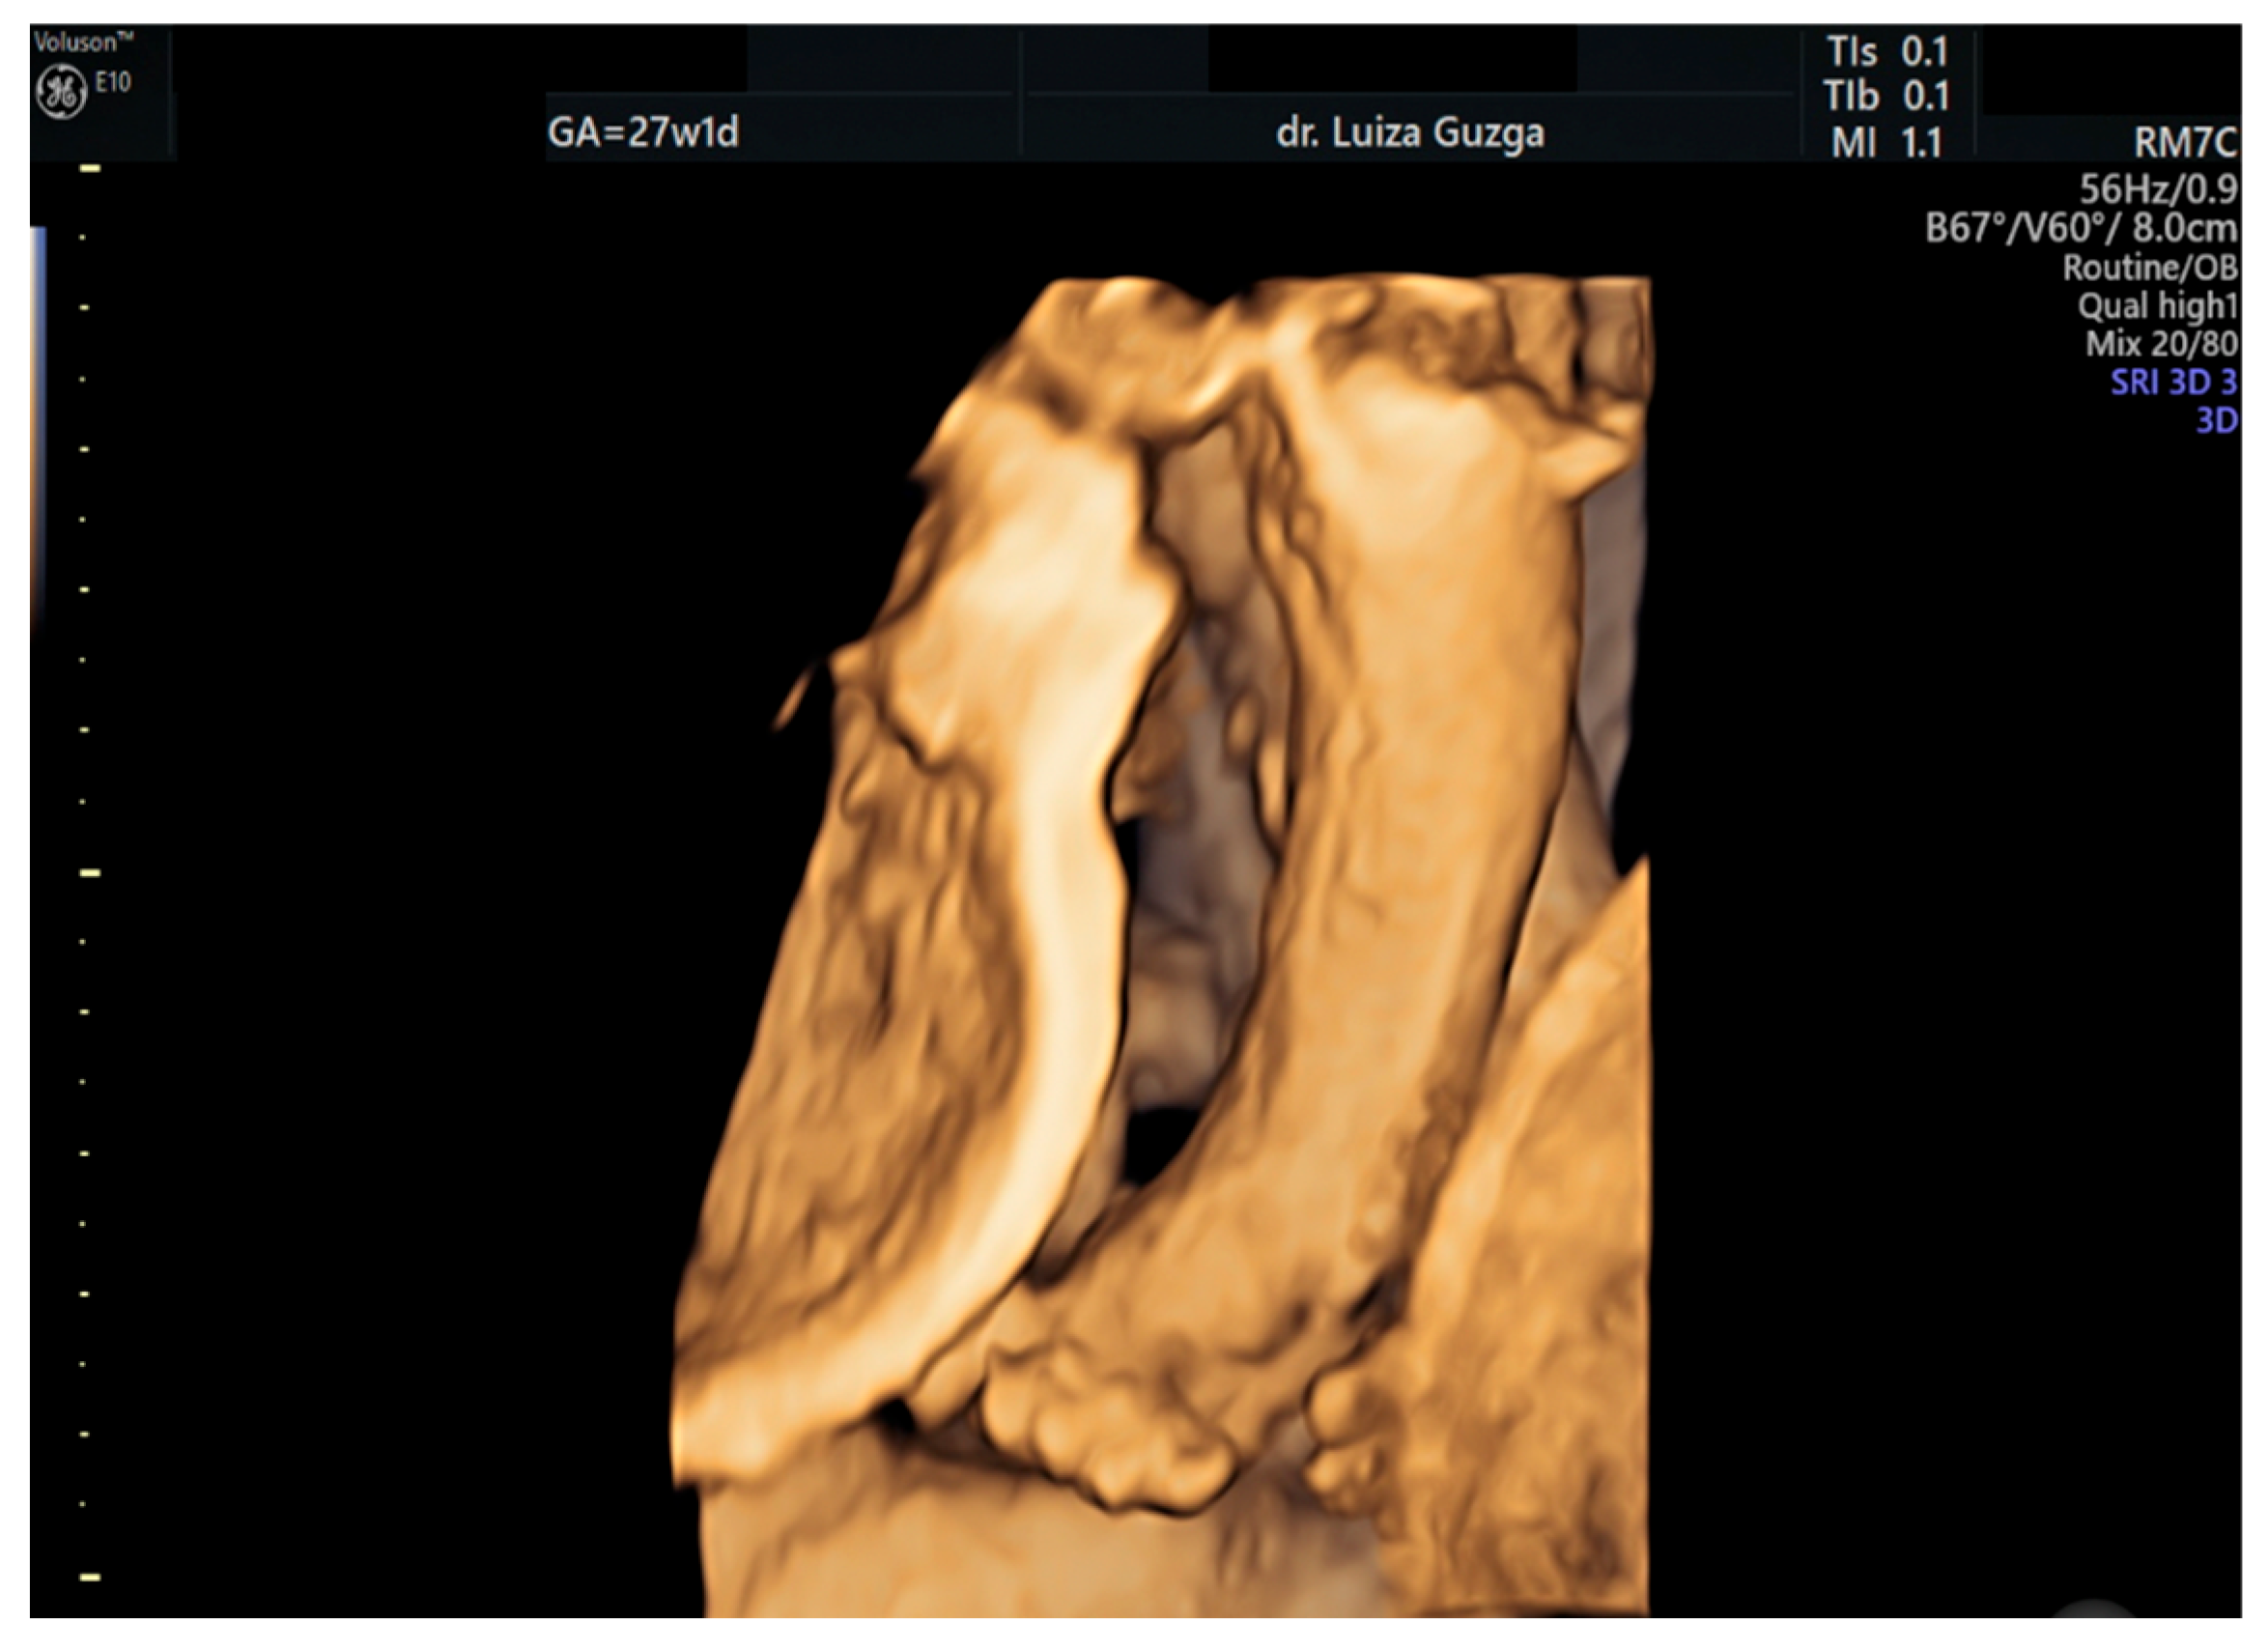

| Broad thumb | - | +++ | +++ | +++ |

| Rocker-bottom feet | - | +++ | +++ | +++ |